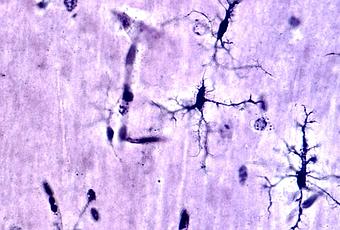

En apparence, la couche la plus externe du cerveau humain, appelée cortex, est un labyrinthe de plis tissulaires. Les sommets ou surfaces surélevées de ces plis, appelés gyri, jouent un rôle important dans le bon fonctionnement du cerveau. Une mauvaise gyrification ou formation de gyri a déjà été impliquée dans différents troubles neurologiques, dont la dépression majeure.

Cet index est une mesure du repliement cortical, dérivée des scintigraphies cérébrales, et qui représente en pratique le rapport entre les surfaces courbes et les surfaces lisses du cortex dans une zone d'intérêt donnée.

Alors que les régions corticales évaluées dans l’étude affectent la régulation émotionnelle, ces schémas de repliement corticaux anormaux, retrouvés chez les patients atteints de dépression, pourraient tout à fait être associés au dysfonctionnement des circuits neuronaux impliqués dans la régulation émotionnelle, ce qui contribuerait à expliquer la physiopathologie du trouble dépressif.

Dans l’attente, l’IGL est documenté comme un marqueur de dépression prometteur, à la neuroimagerie et relativement stable de la dépression, en comparaison des autres biomarqueurs précédemment identifiés. En effet, l’IGL reflète le processus de développement de longue haleine de la gyrification qui ne peut être affecté par l'état d'un patient à un moment donné. D’autant que d’autres caractéristiques cliniques du trouble dépressif majeur, dont la récurrence et la durée de la maladie s’avèrent en revanche associées à une gyrification accrue dans plusieurs autres régions corticales, occipitales et temporales.